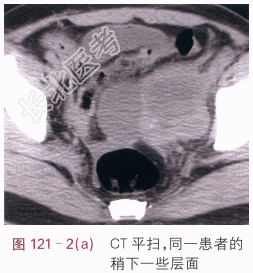

影像学资料如图121-1~图121-3所示。

读片分析:左侧附件区囊实性不规则形肿块,CT增强后实性部分的边缘呈明显强化,中心坏死部分强化不明显,未见肿大淋巴结和腹水征象。多平面重建后可见,左输尿管下段后累及,其中上段积水扩张。